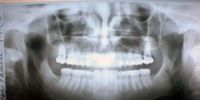

MC-Oral-Health-Services Much still needs to be done to respond to the oral healthcare needs of persons with special needs. (Photo:: Sarah Scicluna / Flickr / Spotlight)